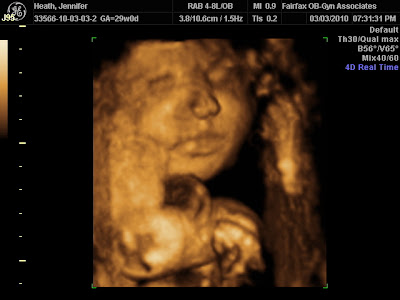

Although I thought the day would never come, it did-- Justin and I (and Baby Jackson) had our 4D sonogram with "Bella Baby" tonight! And, after a dinner that didn't settle well with either of us, it was the highlight of our night (and week). We were so blessed with a sonographer who took her time with us (we paid for 15mins, but got 23mins) in order to produce some awesome images. At first, baby Jax wouldn't cooperate and look at the camera. He was incredibly mobile during the session (kicking, jabbing, rolling) and would hardly be still enough to get photographs. Also (and this is so very endearing), he continuously played with and snuggled with his umbilical cord (the sonographer had never seen it to this extent before). At times, because he was making "sucking" motions, it took like he was teething on his cord. So cute! Several times our sonographer also commented on how very laid back he was. She had me turn to my side twice, she jiggled my belly extensively, she had Justin talk to my belly, and she mashed a lot on my abdomen-- through all of it, Jackson happily played with his cord and didn't turn. Additionally, I learned that he was "seated very low in my pelvis." I certainly hope that's a good thing! EeeK!

As for Baby Jackson's features, here's what we think:

1. He's chubby (has a crease like I did at the bridge of his nose).

2. He has Justin's lips.

3. He has my cheekbones.

5. He has Justin's brow structure (i.e., no "shelf eyes")

* Here are the very best images from tonight * (more on facebook)

This one looks just like my baby pictures!

Beautiful face

Baby Jackson's face

This one looks just like Daddy (lips)